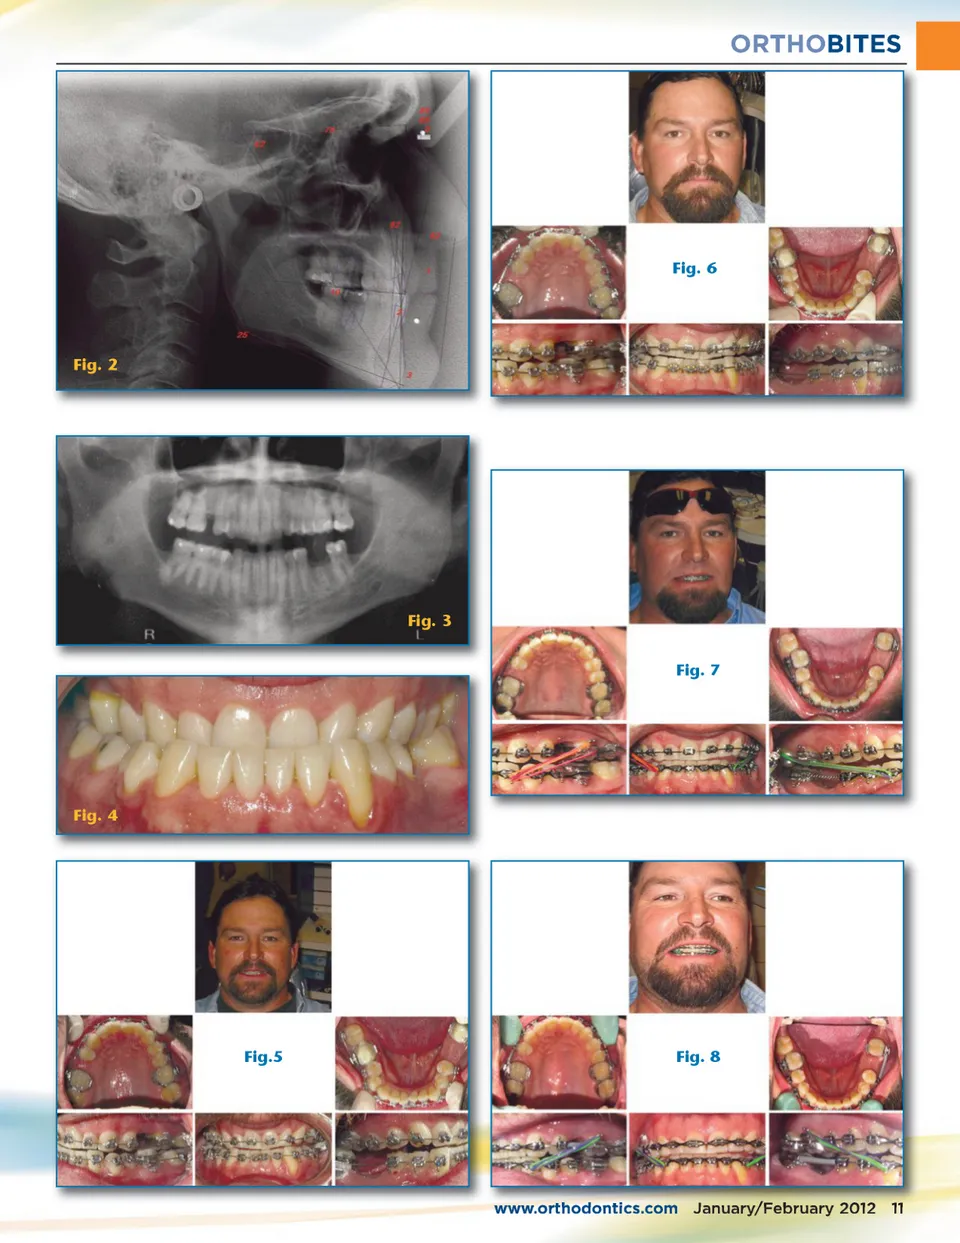

ORTHOBITES Premier Clinical Case Helps Class III Patient By David W. Jackson, DDS, FAGD, IBO, www.orthoplusseminars.com Prepare for Implants M yself and the doctors who participated in the 2010-2011 Premier Orthodontic Clini-cal Courses treated the following case presentation. I am very proud of their accomplishments. I first saw this 42-year-old male in March 2010 as a potential patient for the upcoming Premiere in-office course for 2010. His chief complaint was obvious (Figs. 1 – 4). Several orthodontists had told him that orthognathic surgery was his only option. The man exhibited a full dental underbite, both anterior and posterior. However, he was a skeletal Class I (ANB of .02 and WITS of -2.4mm). He had a concave appearance and exhibited a brachycephalic growth pattern (GoGn – Sn of 24.7 and Y-axis of Fig.1 62.5). His dental arches widths were normal. In addition to his third molars being absent, he was missing his upper right second premolar and lower left first molar. Dental wear and tear was obvious from his malocclusion. We discussed the options of attempting to close the spaces from the missing teeth versus leaving the spaces for implants. The patient and his wife opted for the latter. In March 2010, the class banded and bracketed the patient and placed composite pads to open the bite to prevent bracket failure (Fig. 5). A modified wire series was followed as the patients in the Premiere are normally seen every other month. In May 2010, a large .021 x .025 upper braided nitinol arch wire was placed in the upper arch to employ 3rd order moments of force in the upper arch. A .018 stainless steel arch wire was placed in the lower arch. This created anterior flaring in the upper arch; the round wire had no effect on the lower arch (Fig. 6). In July 2010, the patient was placed in .016 x .022 stainless steel arch wires and was instructed to wear two Class III quarter-inch medium elastics per side at all times. The patient was very compliant (Fig. 7). Also an open coil spring was placed between the lower left second molar and lower left second premolar to maintain the space for the implant and offset the forces from the class II elastics. In December 2010, cushion guard replaced the open coil spring to hold the space for future implants and the patient was instructed to continue wear-ing the elastics (Fig. 8). The patient was monitored every other month and progress was recorded. Pictures are 10 January/February 2012 JAOS